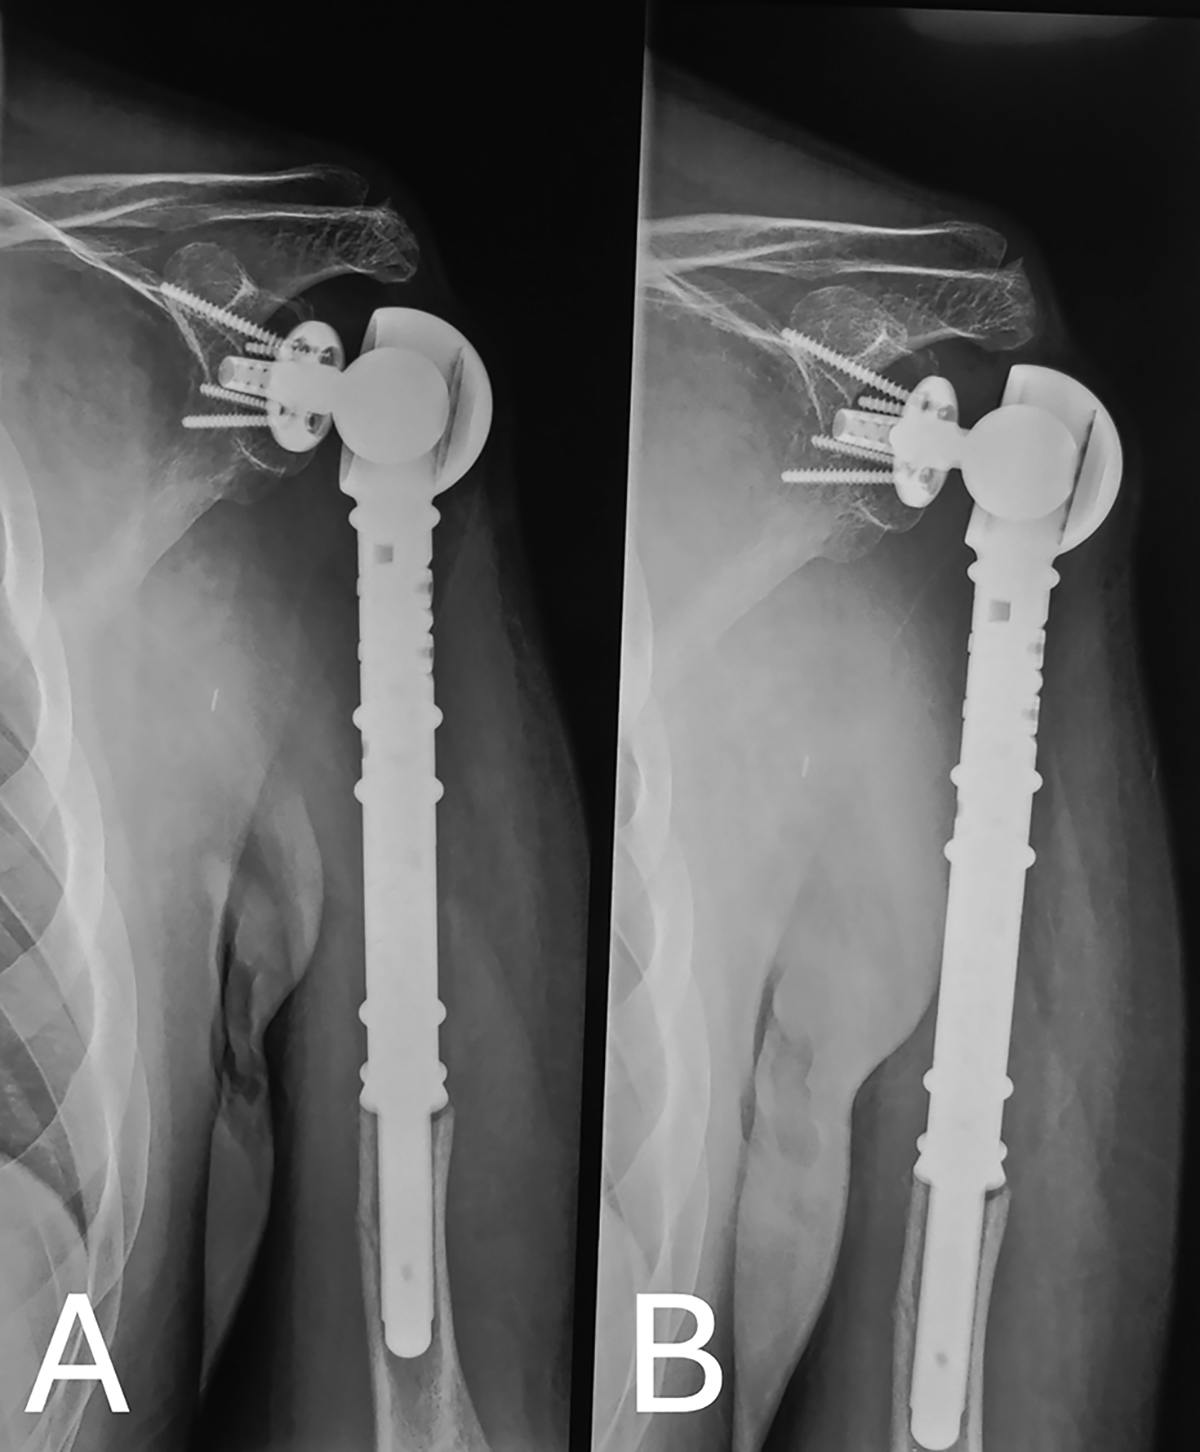

Figure 7

Plain radiograph of the left shoulder at 3.5 years post-operatively showing no signs of loosening or mechanical failure.